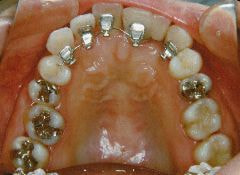

治療例1 (インプラント補綴+矯正)